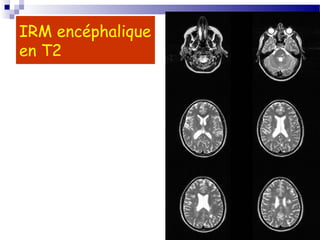

1-L’IRM

 L encéphalique est beaucoup plus sensible que le scanner

pour la détection des plaques.

 Les plaques apparaissent comme des hypersignaux sur les

séquences pondérées en T2, situés dans la substance

blanche, et en particulier dans les régions périventriculaires

et de la fosse cérébrale postérieure. Elles apparaissent iso-

ou hypointenses sur les séquences pondérées en T1. Elles

peuvent s’accompagner d’une prise de gadolinium (traduisant

caractère " actif " des plaques, mais n’entraînent pas

d’effet de masse.

 A l’inverse, certaines poussées ne s’accompagnent

d’aucune anomalie explicative.

 Les hypersignaux en T2 de la susbtance blanche ne sont

cependant absolument pas spécifiques des plaques de SEP,

et peuvent se voir dans de nombreuses autres situations

pathologiques.

 L'IRM permet avant tout d’affirmer la

dissémination spatiale des lésions devant une

séméiologie compatible avec un processus lésionnel

unique.

 Les séquences Flair distinguent mieux les

hypersignaux périventriculaires.

Hypersignaux à l’IRM encéphalique

IRM encéphalique

en T2